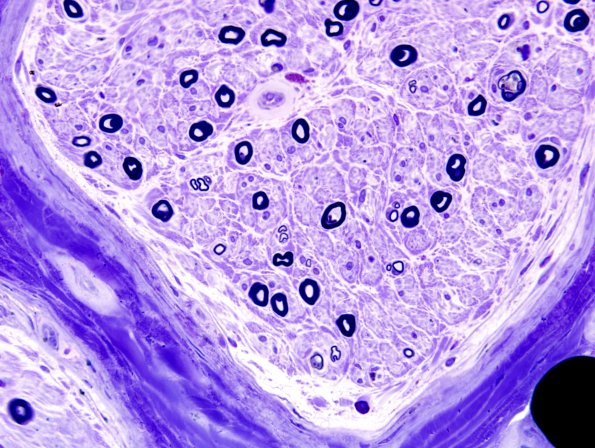

Although there is loss of both large and small myelinated axons the residual axons are mostly large myelinated fiber type.